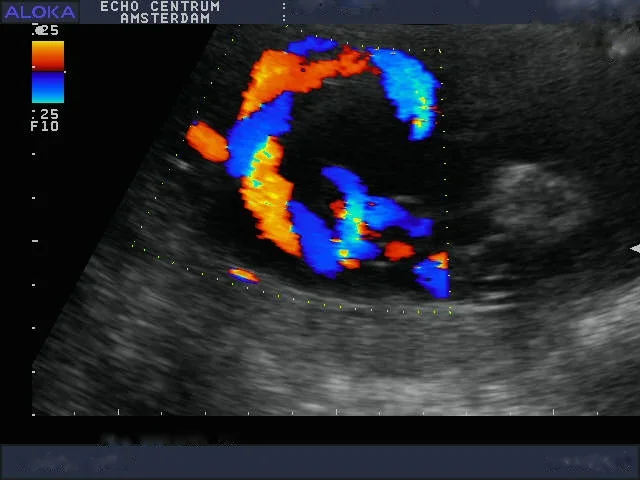

Onlangs had ik een hele leuke ervaring. Ik ben een gepensioneerd gynaecoloog, en was vroeger zeer begaan met mijn verloskundige patiënten. Mijn schoondochter en zoon nodigden mij uit om mee te gaan naar een "pretecho"van dr. Papa in Amsterdam. Wij, gynaecologen, hebben geweldige vooroordelen tegen een zogenaamde pret echo en vinden ze vaak overbodig. Nou dit pakte anders uit. We werden verwelkomd door een bijzonder charmante, leuke en vlot bespraakte Nederlandse Antiliaan: Elvin Papa, arts echoscopist. Daar zat hij in zijn spreekkamer, in een prachtig pand, achter een prachtig echo apparaat, dat voor mijn toenmalige ziekenhuis te duur was om voor ons gynaecologen aan te schaffen!! Alles werd getoond, het hele lichaampje van de baby. Alle organen, het geslacht, hart en bloedvaten noem maar op. Prettig was dat je in 3D een hele goede indruk krijgt van het gezichtje. Het hele onderzoek verliep voorspoedig en was heel relaxed. Papa doet veel aan nascholing en houdt de ontwikkelingen op echo gebied heel goed bij. Echo onderzoek kan heel vervelende zaken aan het licht brengen. Wij hadden een goed nieuws echo, dus dat is feest en lol. Belangrijk lijkt mij wel dat je met een slechte echo bij Elvin Papa in goede handen bent. Hij zal weten hoe je te troosten en hoe je door te verwijzen. Hopelijk hoeft dat niet vaak. Ik wens hem nog veel succes toe.

Bij deze willen wij je nog even bedanken voor de mooie en bijzondere echo die je van onze tweeling hebt gemaakt (de echo lukte zo goed!). Aangezien we ons nogal veel zorgen maakten was de echo precies de positieve input die we nodig hadden. We zijn natuurlijk een beetje beroepsgedeformeerd en wij vonden het schitterend dat je met de moderne technieken (je superecho-apparaat!!) de anatomie van die piepkleine mensjes zo goed kunt zien! Nogmaals ontzettend bedankt.